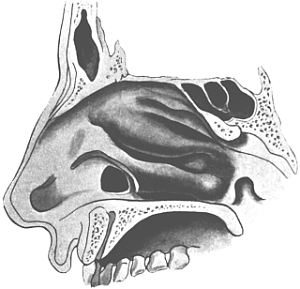

| Operations for Injuries to the Nose—Fractures of the Nasal Bones and Septum, 581. For Congenital Occlusion of the Nostrils, 582. Removal of Foreign Bodies, 584; of Rhinoliths, 586. Operations upon the Turbinals, 586; upon the Inferior Turbinal, 587; upon the Middle Turbinal, 592. For the Results of Syphilis—Sequestrotomy, 594; Post-syphilitic Adhesions of the Velum, 595. For Tuberculosis, 596 | 581–596 |